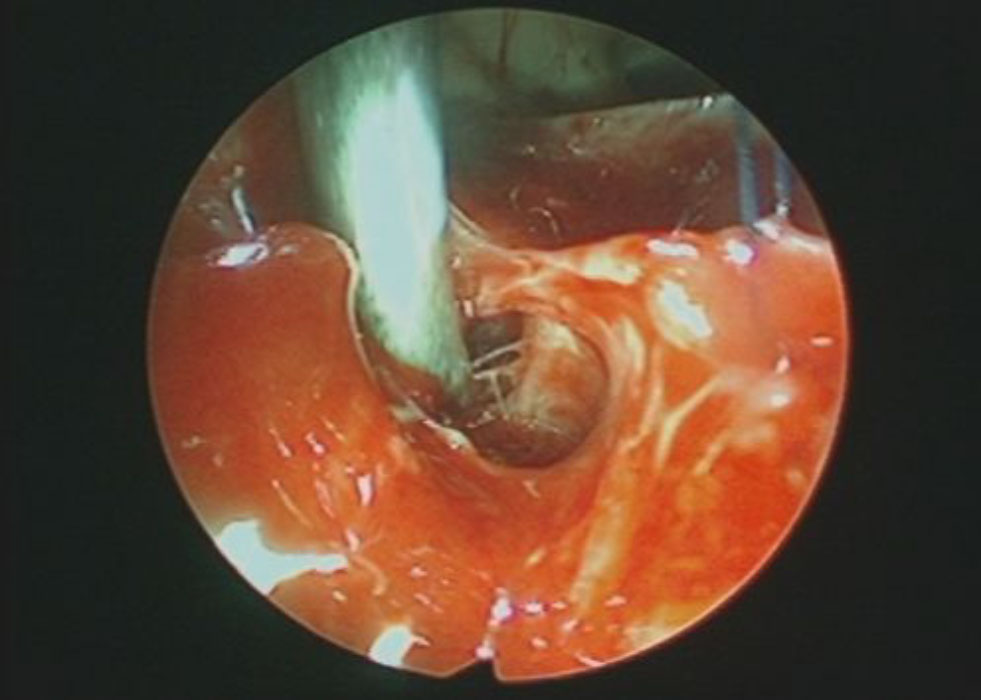

術中写真

摘出 前

摘出 中